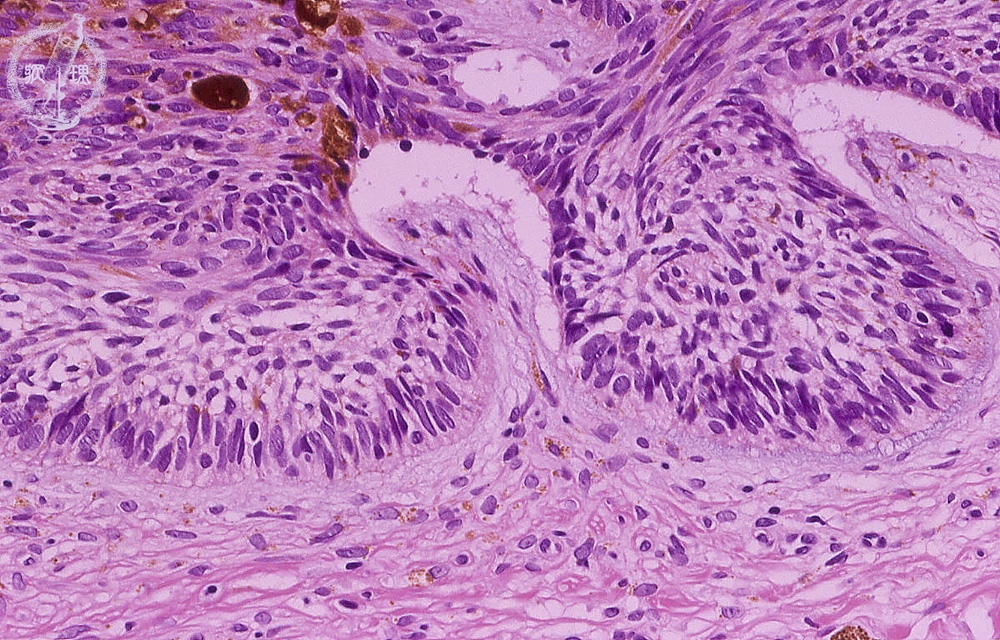

扁平上皮癌

扁平上皮癌は次のように現れることがあります。

- ドーム状のしっかりとした成長

- いぼに似た成長物

- 赤みがかってざらざらしたように見える鱗状の領域

- 開いた傷

- 皮膚の茶色の斑点

医師が基底細胞がんまたは扁平上皮がんの疑いがある場合、皮膚生検を指示することがあります。この手順には、皮膚のサンプルを採取し、検査のために研究室に送ることが含まれます。皮膚サンプルの検査により、皮膚がんの診断を確認できます。